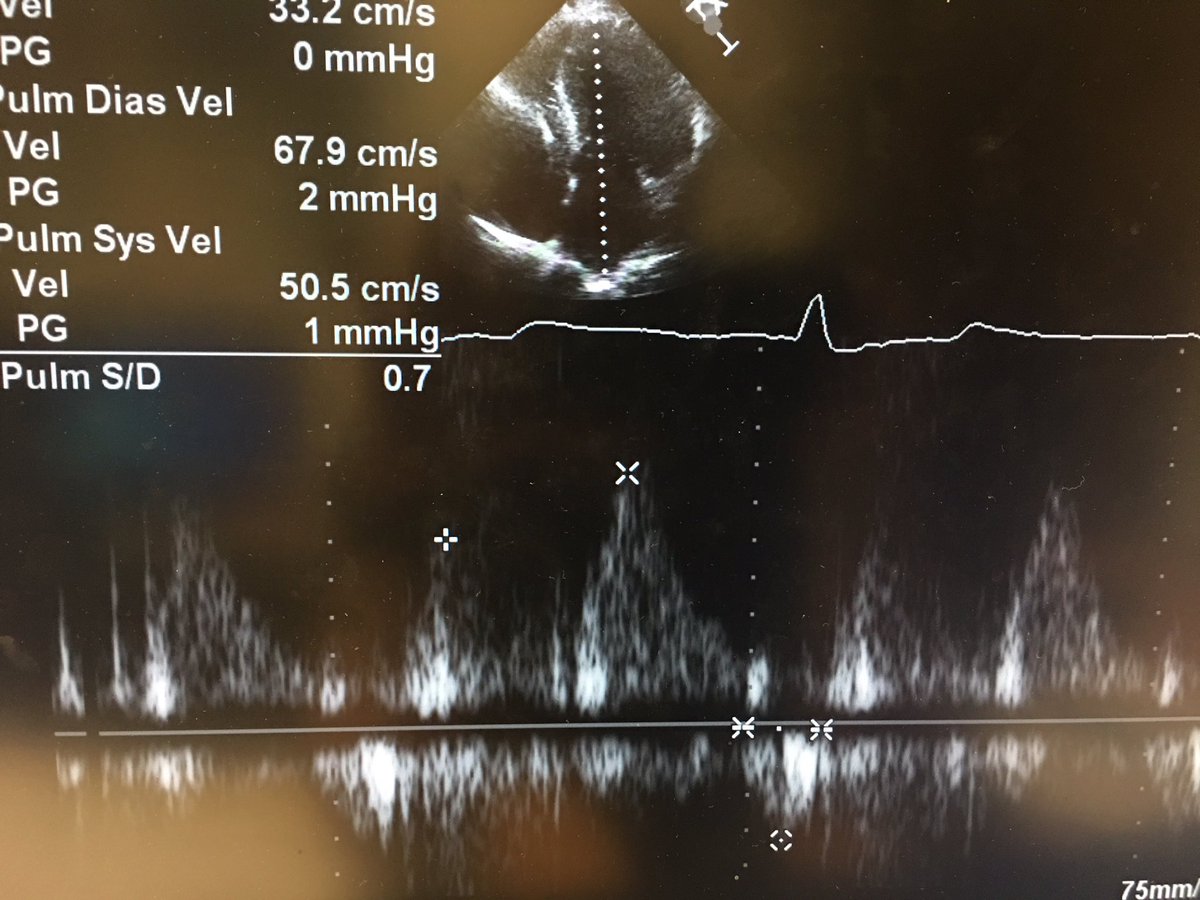

7) and lastly, perhaps unsurprisingly, there was pseudonormal filling with high filling pressures. #hocm #echofirst